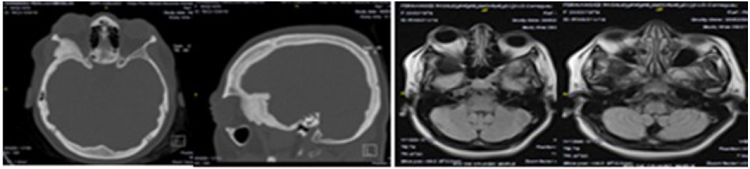

En la tomografía axial computarizada de cráneo simple se visualizó la lesión extra-axial hiperdensa a nivel de la pared lateral de la órbita, con extensión extra e intraorbitaria con compresión de estructuras adyacentes lo que provocaba desplazamiento anterior del globo ocular. En la resonancia magnética de cráneo simple se realizaron cortes axiales y sagitales, se evidenció una lesión extra-axial hipointensa, a nivel de la pared lateral de la órbita con extensión extra e intraorbitaria con comportamiento similar a la tomografía axial computarizada (Figura 1).